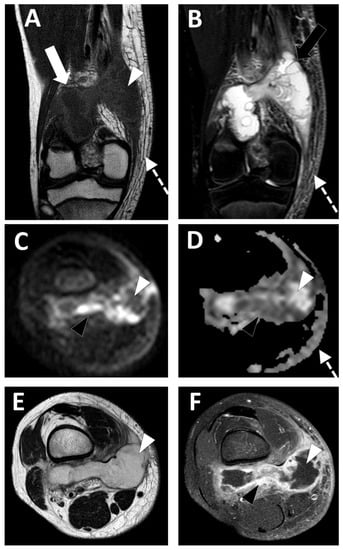

2.5. Infectious Myositis

- Chun, C.W.; Jung, J.-Y.; Baik, J.S.; Jee, W.-H.; Kim, S.K.; Shin, S.H. Detection of soft-tissue abscess: Comparison of diffusion-weighted imaging to contrast-enhanced MRI. J. Magn. Reason. Imaging 2018, 47, 60–68. [Google Scholar] [CrossRef]

- Harish, S.; Chiavaras, M.M.; Kotnis, N.; Rebello, R. MR imaging of skeletal soft tissue infection: Utility of diffusion-weighted imaging in detecting abscess formation. Skelet. Radiol. 2011, 40, 285–294. [Google Scholar] [CrossRef]